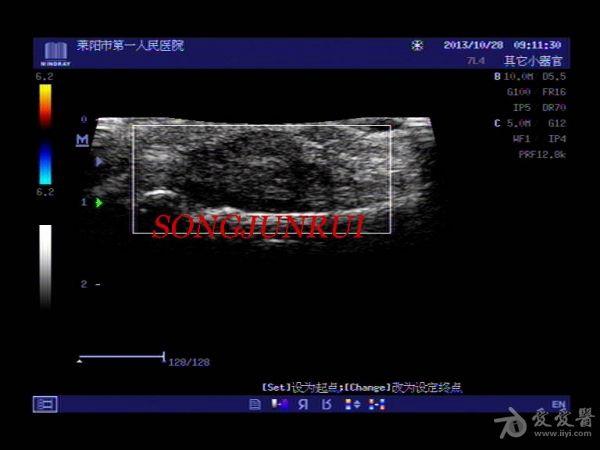

超声入门贴202-----手指腱鞘巨细胞瘤(手术病理)

女,43岁,右手食指中节近节指关节处明显肿胀一年,近一个月增大明显来诊

触诊:有结节感,加压疼痛明显

手术剖开见肌腱附着结节样淡黄色实性组织,范围较广泛,边界不清,病理电话随访腱鞘巨细胞瘤。